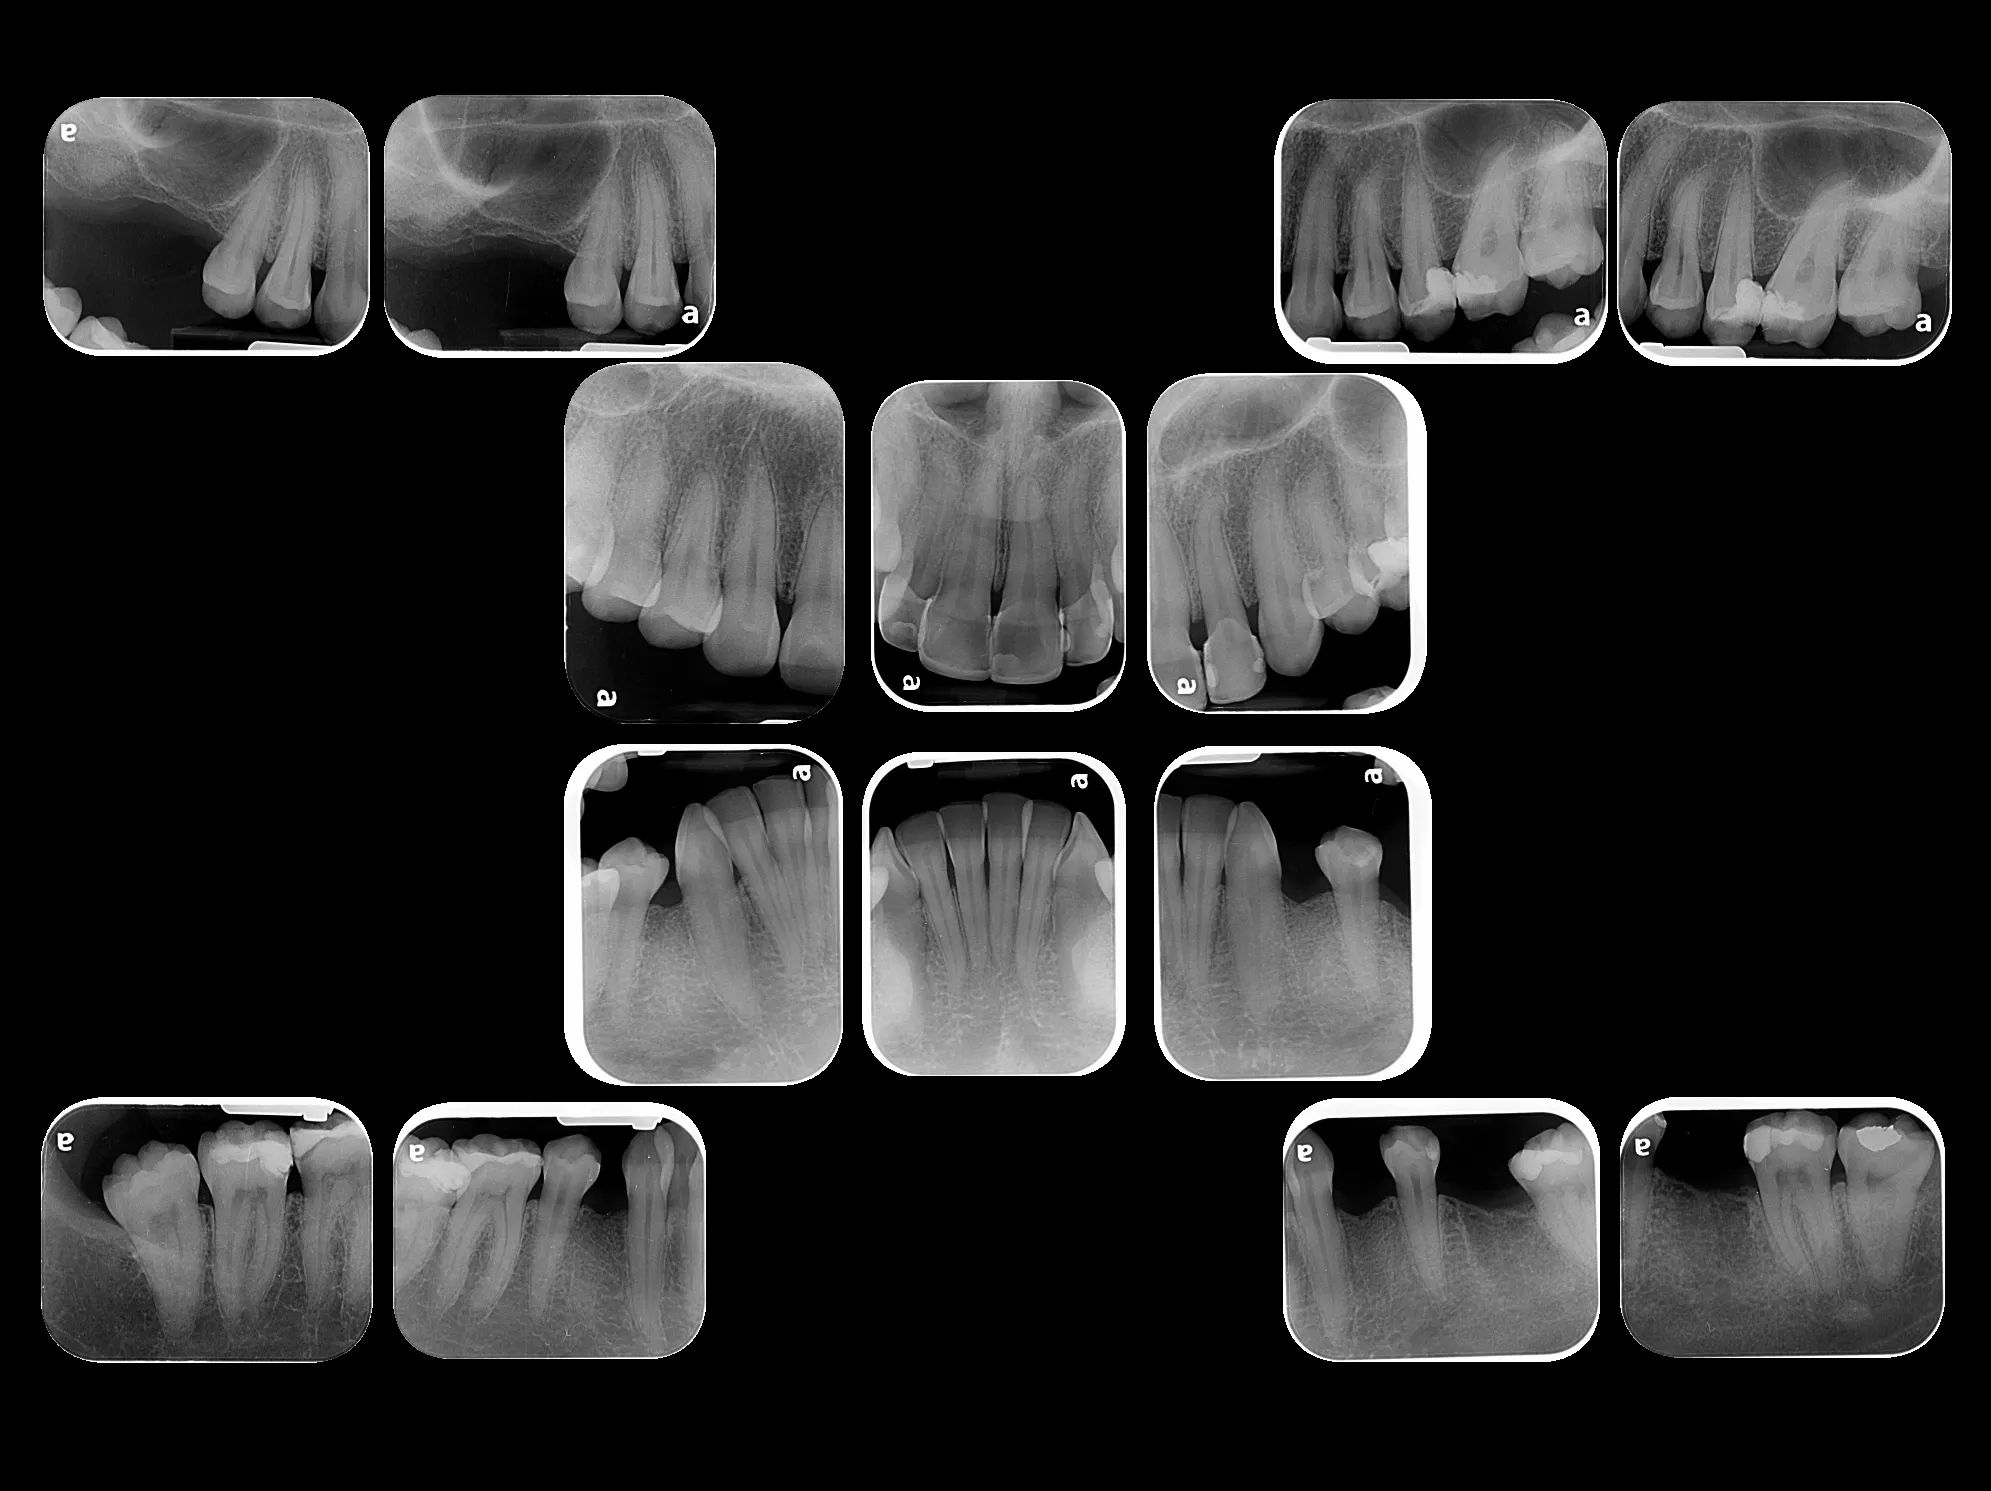

Radiografía Intraoral

La radiografía intraoral permite observar con gran detalle los dientes y las estructuras que los rodean. Es una herramienta fundamental para detectar caries, infecciones, fracturas, alteraciones en la raíz dental o en el hueso de soporte.

En MS Radiología Dentofacial, utilizamos equipos digitales de alta precisión que reducen la exposición a radiación y garantizan imágenes nítidas para un diagnóstico confiable.

• Ideal para tratamientos de endodoncia, implantología y control preventivo.